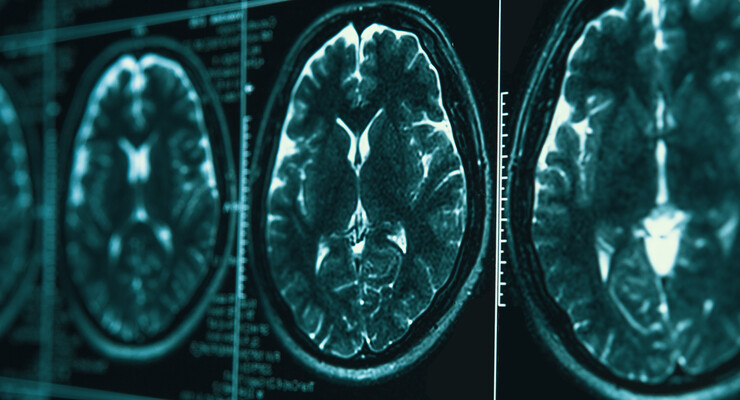

- Metachromatic Leukodystrophy, commonly known as MLD, is a genetic disorder that affects the white matter, or myelin, of the brain and the central nervous system. The life expectancy is usually less than 10 years after diagnosis.